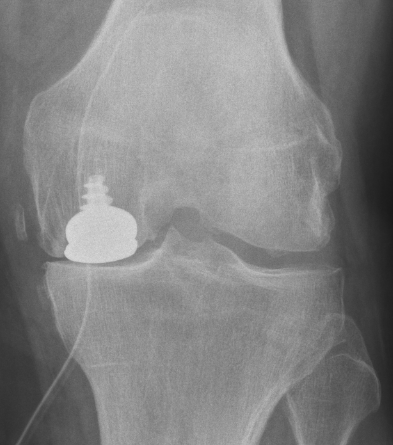

Exemple 1: homme de 61 ans, usure surtout femorale:

ci-dessus: images radiographiques après l'opération: à gauche, on voit le "patin" femoral de face; à droite, on le voit de profil, et on remarquera la vis en titane qui permet d'ancrer la surface en acier poli dans l'os.